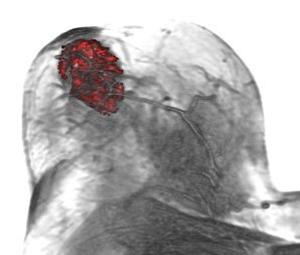

Breast cancer is the second leading cause of cancer deaths in women today. Although X-ray mammography is regarded as the most widely used method for early detection of breast cancer, the use of Contrast Enhanced MRI (CE-MRI) has gained considerable attention in the past years. Especially, Dynamic CE-MRI (DCE-MRI) considerably improves tumor classification by analyzing the flow of contrast agent within the breast tissue. In this paper we present MammoExplorer, an advanced CAD application that combines advanced interaction, segmentation and visualization techniques to explore Breast DCE-MRI data. In addition, we present a novel graphical representation of DCE-MRI data, new segmentation approaches, and a new way to explore temporal data.Additional Files and Images